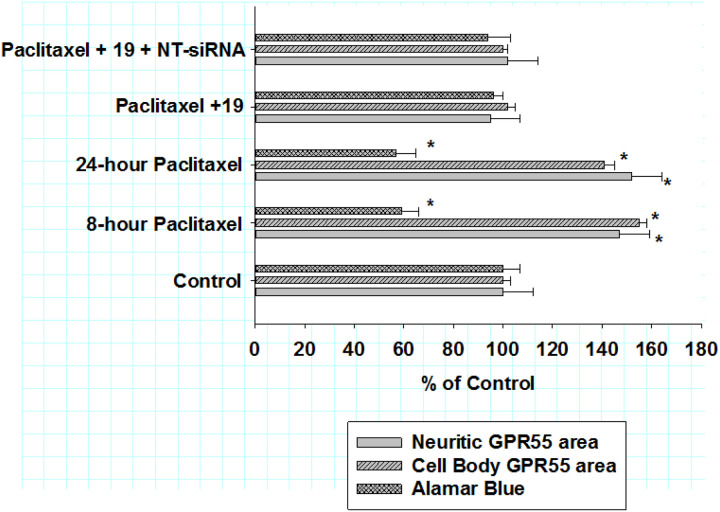

Non-targeting siRNA and anti-inflammatory action of KLS-13019